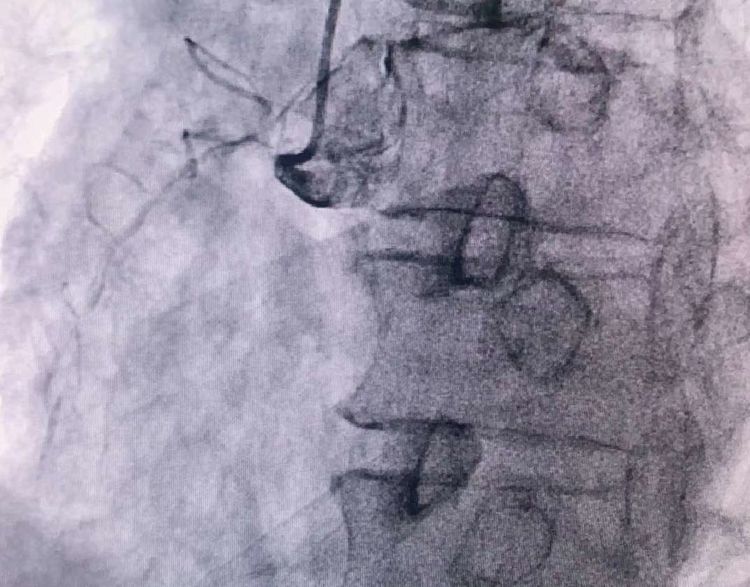

患者前降支、右冠100%閉塞,LCX中段60%狹窄。命懸一線,手術(shù)臺(tái)上持續(xù)胸痛。和患者家屬及時(shí)溝通后,決定行PTCA術(shù)。血壓低至60/40mmHg,在主動(dòng)脈內(nèi)球囊反博的支持下緊急行PCI術(shù)。軌道很快建立,導(dǎo)絲也及時(shí)通過病變血管,噩夢來了,患者發(fā)生室顫了。在吳棟梁院長的指揮下,李陽主任和心臟團(tuán)隊(duì)的成員共同努力下,除顫、冠脈內(nèi)溶栓、多個(gè)球囊輪流上陣,患者病情平穩(wěn)了,罪犯血管及時(shí)開通,血流恢復(fù)三級(jí)血流。平安下臺(tái),準(zhǔn)備擇日再處理冠脈情況。